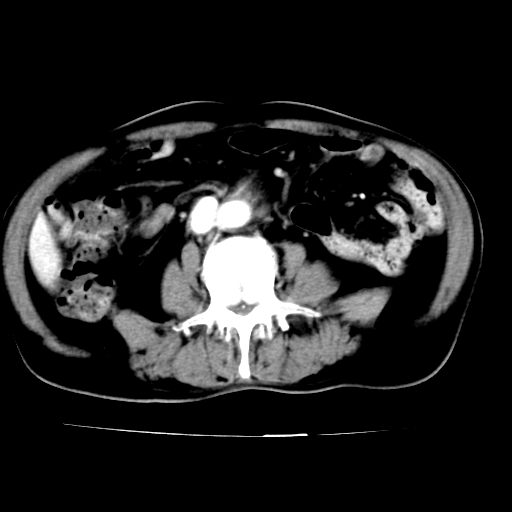

男,75岁,腹痛月余,彩超发现脐周腹主动脉异常回声。临床诊断:腹主动脉瘤。

ct诊断:右骼总动脉囊性动脉瘤并瘤内附壁血栓形成,与下腔静脉之间形成动静脉瘘。

请问各位老师:能排除动脉瘤破裂的可能吗?

各位老师注意到下腔静脉的充盈缺损了吗?注意到动静脉漏了吗?

当时是扫描的标准动脉期,可是下腔静脉与腹主动脉同步强化且幅度一致。所以我想动静脉瘘是存在的。